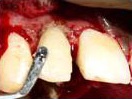

Splinting of Fracture

Fragments with direct

Composite Veneering

In the process of Removal

of Pulp after access preparation

then Cleaning and Shaping done.

Single sitting RCT

Completed after Sectional

Obturation.

Root and Crown Fragments

are splinted with Glass

Fibre Post. Resin Cement and

Light Cure Composite

are used for this purpose.

Finished palatal view

of the tooth. Stitches can be seen.

Finished Labial view

Stitches can be seen.